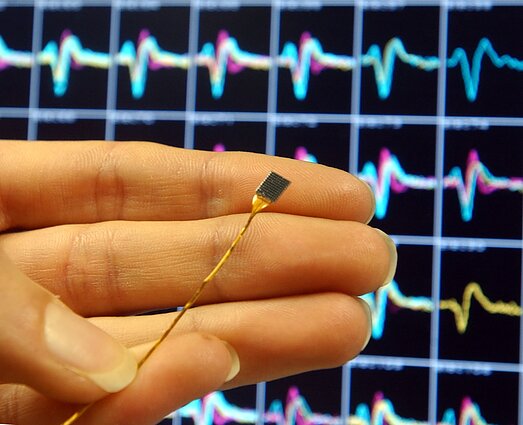

Šanchajaus bendrovės „Neuracle Medical Technology“ sukurtam įrenginiui NEO suteiktas oficialus Nacionalinės medicinos prietaisų asociacijos patvirtinimas.

Esminis technologijos veikimo principas – sąsaja tarp smegenų ir kompiuterio. Aštuoni elektrodai registruoja elektrinį aktyvumą, kai žmogus įsivaizduoja judinantis ranką, tuomet signalai perduodami į kompiuterį, kuris juos iššifruoja ir panaudoja liepdamas ant paralyžiuotos rankos uždėtam egzoskeletui atlikti norimus judesius.

Monetos dydžio NEO įrenginys – minimaliai invazinis implantas. Jis įtvirtinamas kaukolėje, o aštuoni elektrodai ne integruojami į pačias smegenis, bet padedami ant jų dangalo vienoje galvos pusėje.

„Kaip sakant, lazda su dviem galais – tokio tipo prietaisas gali iš karto mažiau informacijos nuskaityti ir mažiau ko nors padaryti, bet iš tos pusės automatiškai mažesnis yra visokiausių rizikų, uždegimų, atmetimo pavojus ir panašiai“, – pastebi Vilniaus universiteto Gyvybės mokslų centro (VU GMC) profesorius Aidas Alaburda.

Todėl šiuo metu tokių implantų, kokius vysto milijardierius E. Muskas, nauda dažnai vertinama labai atsargiai. „Neuralink“ naudoja labai plonas elektrodų gijas, kurios įvedamos tiesiai į smegenų audinį. Tai leidžia gauti aukštesnės raiškos ir tikslesnius signalus, nes elektrodai yra arčiau neuronų, tačiau kartu padidina chirurginę ir biologinę riziką bei kelia iššūkių dėl ilgalaikio patikimumo“, – teigia mokslininkė.